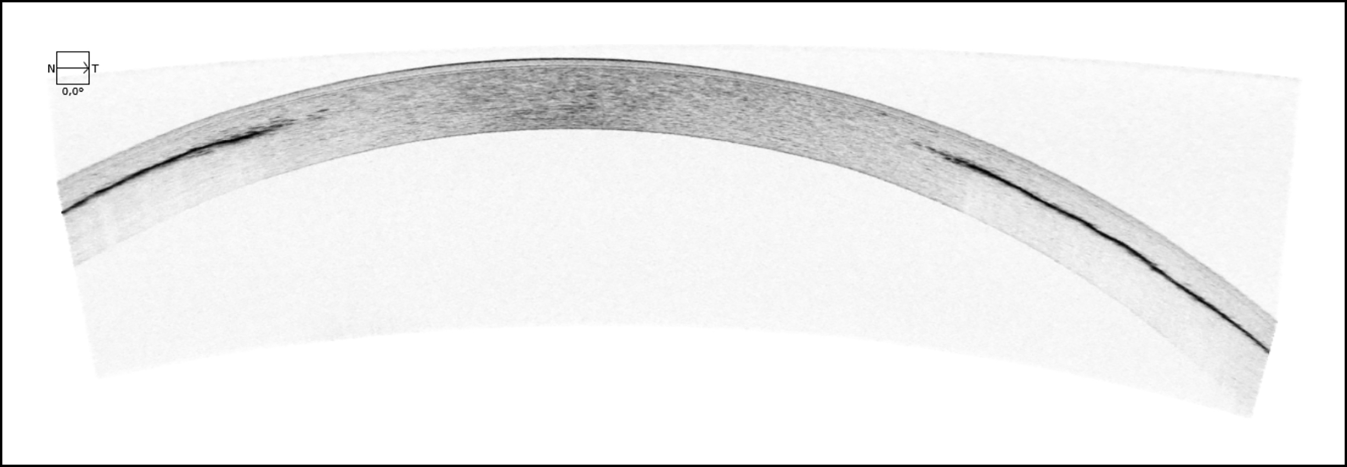

Abb. 2

Optische Kohärenztomographie (OCT) der Hornhaut des linken Auges nach Keratopigmentierung mit Darstellung der intrastromal eingebrachten Pigmente als dichte, hyporeflektive Lamelle

Sehr deutlich kommen in der Hornhaut-OCT die hier dunkel in Erscheinung tretenden Farbpigmente peripher im Hornhautstroma zur Darstellung. In der Hornhauttopographie fallen ein zentral irregulärer Astigmatismus sowie eine scheinbar konzentrische Aufsteilung der peripheren Hornhaut auf.